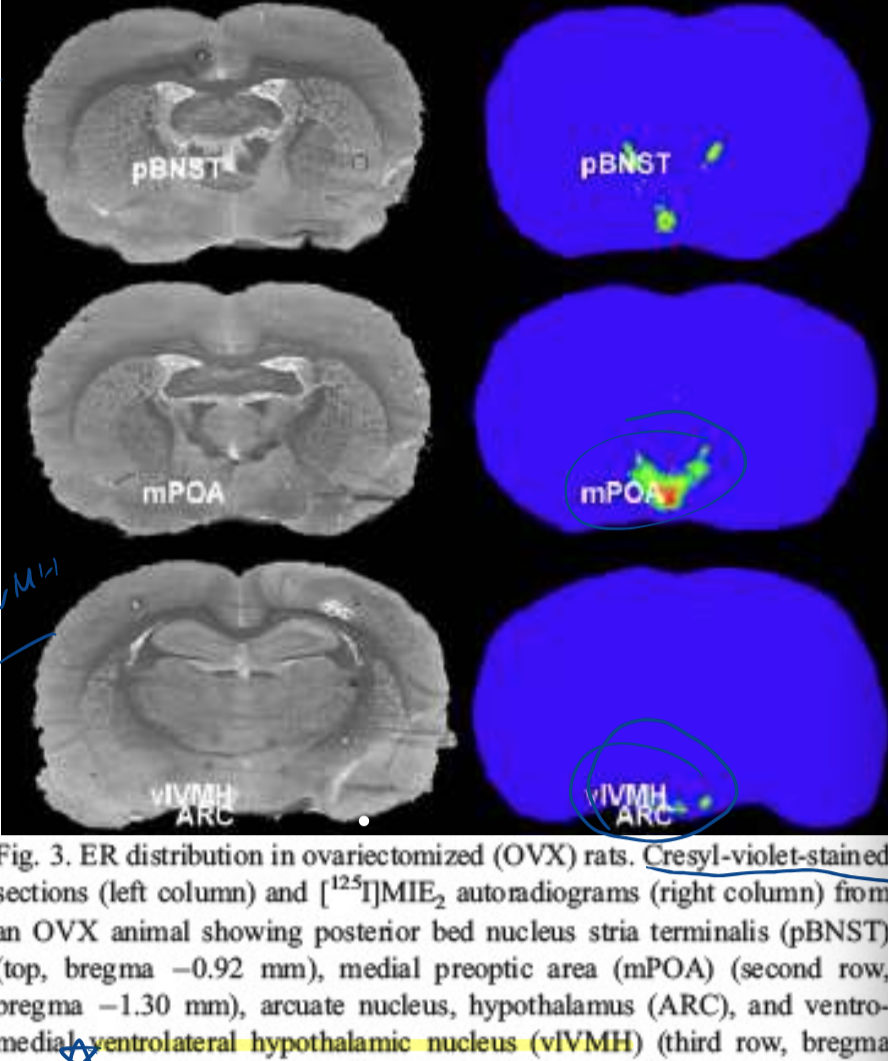

estrogen receptors in brain

-autoradiography with labeled E2 used

-ERs in vlVMH (ventrolateral ventromedial hypothalamic nucleus) critical especially for male sexual behavior

-X ray shows anything that binds to estradiol

autoradiography